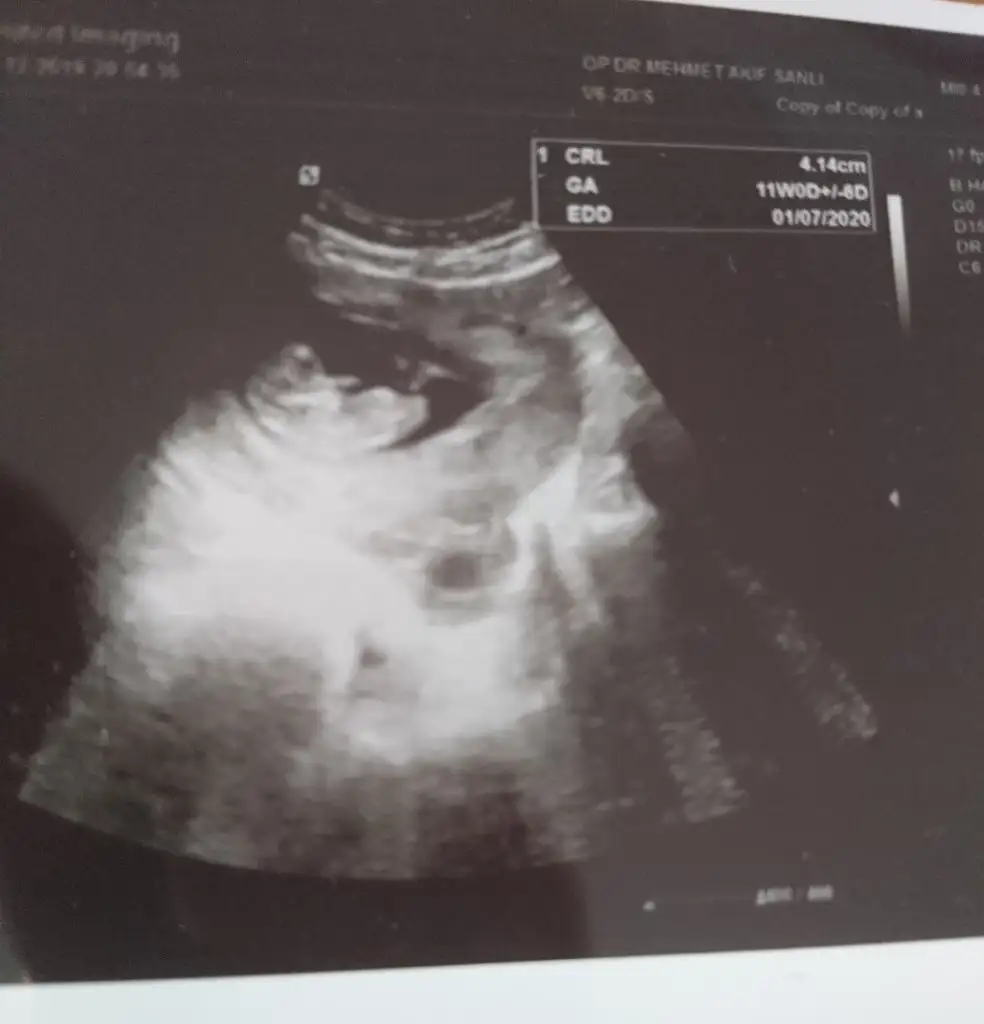

• 0ECABA96-7800-45A3-B34E-E6A90A9D5C9A.webp

0ECABA96-7800-45A3-B34E-E6A90A9D5C9A.webp

27,9 KB · Görüntüleme: 102

Ikra meyra Ikra meyra canım burda 12+2 ultrasona göre. Tekrar gönder demiştin var mı acaba bi şansım bu sefer 😂